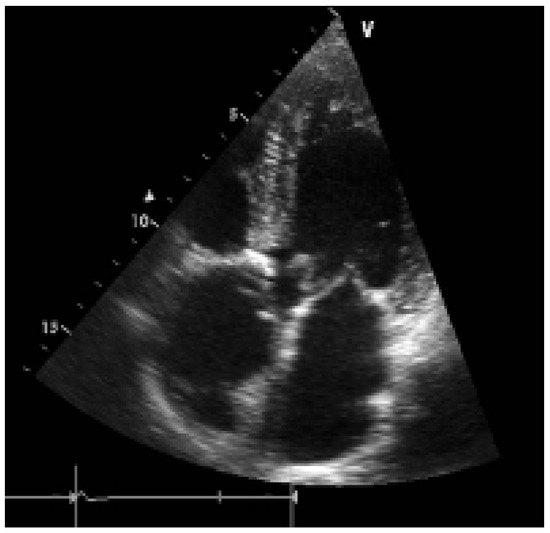

While substantial progress has been made over the past decade in the medical treatment of heart failure, certain patients fail to respond to optimal treatment despite the availability of excellent drugs. Cardiac resynchronisation therapy, or multisit...